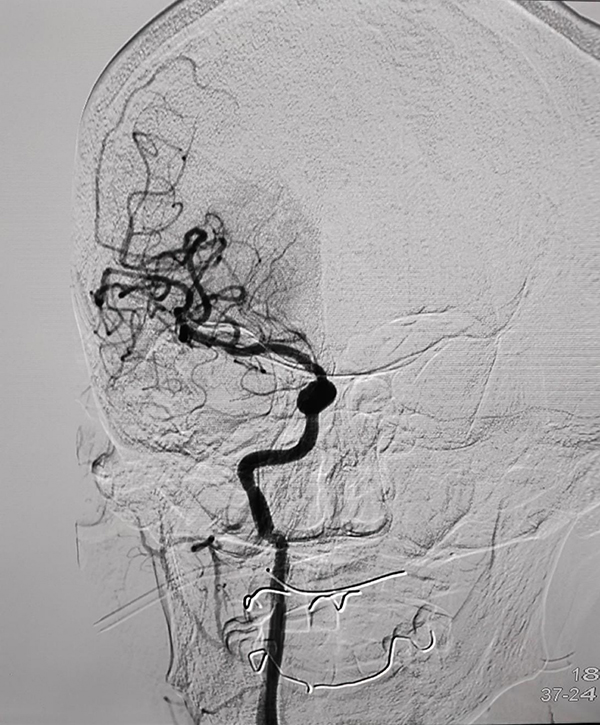

CTP检查结果提示,姬阿姨颅内核心梗死体积约9.6ml(红色区域),但低灌注区域体积高达81ml(绿色区域)(图2),低灌注区域越大,代表可挽救的脑神经细胞越多,手术开通的价值越大,可见患者颅内低灌注区域远远大于核心梗死区域,颅内动脉取栓术手术指征进一步明确。在与患者家属积极沟通,征得家属同意后,王建峰主任团队在国家级高级卒中中心李健主任的指导下,急诊进行了全脑血管造影术+颅内动脉取栓术,术中证实右侧大脑中动脉起始段闭塞(图3),并急诊进行了右侧大脑中动脉取栓术,术中抽拉出一块暗红色血栓,术后可见右侧大脑中动脉血流通畅(图4)。术后1周,在神经内科一病区医护人员的精心照料下,姬阿姨完全康复,说话言语清晰,对答切题流畅,四肢肌力活动恢复正常,现已康复出院。

图2

图3